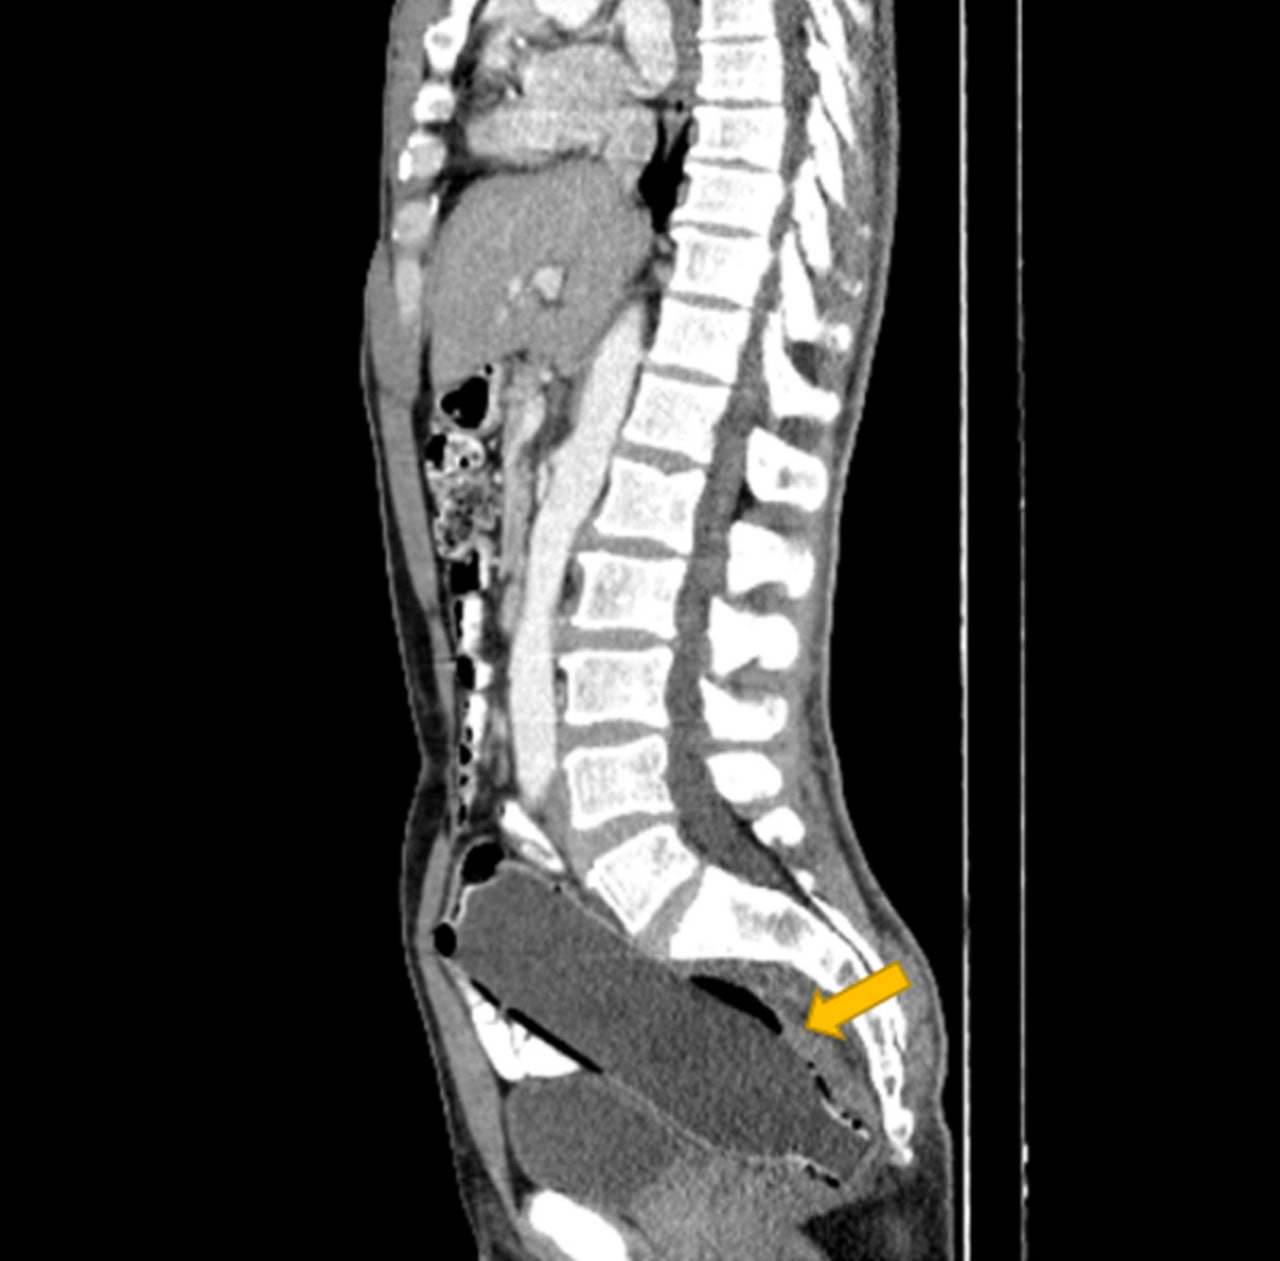

《紐約郵報》報道,伊朗一名50歲男子因腹部劇烈疼痛,導致出現便祕及多日未進食的情況,就在照完X光後,發現直腸內竟藏有一個完整的膠樽。

而這宗個案也被記錄在《臨床病例報告》的期刊中,其中負責診治的伊瑪姆霍梅尼醫院(Imam Khomeini Hospital)醫生指出該名患者患有憂鬱症,並說道腹內的瓶子是先由底部進入肛門,之後才卡在直腸內。

醫生也透露,原本想藉由小瓶口當作施力點,順勢將其拉出,但最終仍不幸失敗,醫生只好改透過手術,在不傷及腸道的前提下,慢慢將膠樽拉出。